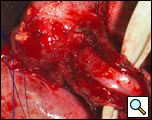

The surgical approach is a left posterolateral thoracotomy, entering the chest over the bed of the unresected 7th or 8th rib. On entering the thoracic cavity, the pulmonary ligament is divided and the lung is packed out of the way superiorly. The epiphrenic diverticulum is often found at the level of the inferior pulmonary vein. The pleura over the esophagus is divided allowing the esophagus to be gently mobilized. Penrose drains are used to encircle the esophagus superior and inferior to the diverticulum to facilitate the dissection (Figure 3). The diverticulum often arises to the right side necessitating rotation of the esophagus to clearly visualize the neck of the diverticulum. The diverticulum and its base are carefully dissected from the adjacent esophagus (Figure 4). Both vagus nerves are clearly identified and preserved during this maneuver. Once the diverticulum base is defined, a 40 Fr bougie is introduced across the gastroesophageal junction. This is performed under direct vision with the surgeon closely monitoring the safe passage of the bougie.